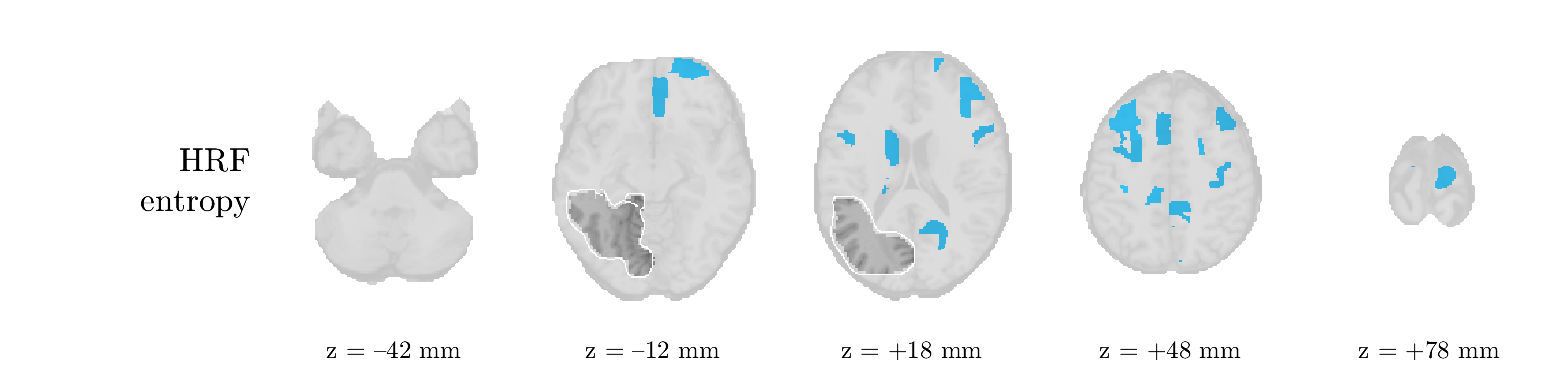

We analyze the solution with sources. Figure 1 shows the EEG signatures and HRF waveforms. One of the sources is highly correlated to the MWF reference (in grey), which was already known from Table B.3. This IED-related source had a typical low-frequency spectrum, which is expected for the typical spike-and-wave interictal discharges. The topography is relatively diffuse, although the highest amplitudes are mostly in the left hemisphere. This is in accordance with the lateralization of ictal onset zone (left temporal lobe, cfr. Table 1). There are some noteworthy observations to be made about some of the other components. The fourth has an unusually sharp spectrum, is mainly localized on two nonadjacent center electrodes, and is sustained for a single period of many seconds Hence, this component likely captured an artifact (of yet unknown origin), although we spotted no large-amplitude changes in the EEG itself. Similarly, the third source is only present at one frontal electrode, and exists in a frequency range above 20 Hz. It might represent a muscle artifact, e.g., due to frowning or twitching of some muscles in the forehead. The HRFs of all ROIs are shown in Figure 1(b). Two of the basis functions seem to have converged to a very similar waveform, which is an unfortunate possibility if two initial HRFs are too close to the same local optimum in their respective parameters. This reduces the expressive power of the basis set, which is clearly visible, since many ROIs have a nearly identical HRF. One of the twenty ROIs with the highest-entropy HRF overlapped the IOZ, although clearly this HRF (bold line) is not among the most dissimilar waveforms for this patient. This is also visible in Figure 2: both the HRF entropy and extremity maps show a small overlap with the delineated IOZ. Despite the good correspondence in the EEG domain, no significant (de)activation of the IED-component is found inside the IOZ.

We analyze the solution with sources, and show the results in Figure 3 and 4. As for patient 1, we found a source which is strongly correlated to the MWF envelope, and which had a mostly low-frequency behavior characteristic for spikes. The topography is mostly uninformative, and does not clearly correspond to the patient’s clinical data. The third source is mostly present at both sides of the head, is very sparsely active in time, and has a high-frequency content: this is most likely an artifact due to the neck muscles. Again, there is one of the highest-entropy HRFs which belongs to a ROI in the IOZ. Now, the waveform is clearly resolved from the other HRFs, through the strong initial dip (before 0 seconds). Such a dip is sometimes observed in HRFs, but its underlying physiological mechanism is not yet fully understood. It is possible that this dip reflects altered vascular autoregulation near the IOZ (cfr. the explanation in the Section 1 of the main text), or a rapid depletion in oxygen due to IED generation (before the IED becomes visible on the EEG). Figure 4 furthermore shows that the IED-related component is significantly active in parts of the IOZ, and deactive in others. As mentioned earlier, this deactivation may or may not be due to errors in sign correction. Interestingly, the ROI with the high alteration in neurovascular coupling is distinct from both the activated and deactivated ROIs.

We analyzed the solution with sources, and show the results in Figure 5 and 6. There is one source which is mostly correlated to the reference (but not extremely, see also Table B.3). This source had a right-temporal focus, conform the diagnosis in Table 1. The second source illustrates the phenomenon of an erroneous sign exchange between the spatial and spectral profiles. Also one of the HRFs has a negative polarity, which is a failure of the sign correction procedure (in this case, because there is exceptionally no positive overshoot). However, the HRF variability metrics are still interpretable, and indeed two ROIs among the ones with the highest-entropy HRFs overlap with the IOZ. The IED component is significantly active in a tiny portion of the IOZ (cfr. Figure 6). The second source is significantly active in symmetrical parts of the parietal lobe. Given its ongoing fluctuation over time, we hypothesize that this source captures a resting state network (RSN).

We analyze the solution with sources, and show the results in Figure 7 and 8. There is a clear IED-related component, with a very high correlation to the MWF reference, a typical spectrum, and an anterior-temporal focus, which corresponds very well to the patient’s diagnosis (cfr. Table 1). The fifth source seems present at only one channel, and has spectral harmonic at Hz and Hz. One of these peaks is reminiscent of the fourth component in patient 1. As Figure 8 shows, the HRF entropy and extremity prove to be strong biomarkers for the IOZ in this case, and also the significant IED activation and deactivation allow correct localization. In Figure 7, it is clear that some HRFs may still have the wrong sign, which means that the interpretation of ‘active’ and ‘deactivated’ is flipped in those ROIs. Hence, regions of significant deactivation are in fact significantly activated. The fourth source had a significant overlap with the auditory RSN, and its spectrum reveals activity in the band.

We analyze the solution with sources, and show the results in Figure 9 and 10. One source is strongly correlated to the MWF, while the other source is likely an artifact, given its very sparse temporal profile. Both sources coincide at one high-amplitude peak, by which we infer that this is probably an artifactual period in the signal. Indeed, when inspecting the original EEG signals, we found high-frequency muscle artifacts at these times. This source also had no significant activation in its spatial map, which corroborates its non-neuronal origin. The IED-related source had a broader spectrum than most other cases, and an uninformative topography. None of the ROIs with high-entropy HRFs is located in the IOZ. The pseudo t-map provides correct localization of the IOZ, however.

We analyze the solution with sources, and show the results in Figure 11 and 12. We found a clear IED-related component, with a characteristic spectrum and a topography which is backed up by the patient’s diagnosis (left anterior-temporal IOZ). The fourth source has a very similar topography and spectrum to the fifth source in patient 5. One HRF inside the IOZ had a high-entropy, and is distinguishable from the others by its very sluggish waveform, i.e., it is smeared out in time, with no sharp over- or undershoot. Also the pseudo t-map provided an accurate localization of the IOZ. Notably, in this patient, the extremity metric misses the deviating HRF in the IOZ (while the entropy metric picks it up). The second source overlapped with the frontal part of the default mode network (DMN), and is active in the and low bands.

We analyze the solution with sources, and show the results in Figure 13 and 14. We found two components which had correlated time courses. At the time of the peaks, we found higher-amplitude events in the EEG with dubious origin, hence they may or may not be artifacts. One of both components is more strongly correlated to the MWF, and its activation is concordant with the IOZ. The second component shows high overlap with the sensorimotor network. For this patient, none of the IOZ’s ROIs had extreme values of either HRF metric.

We analyze the solution with sources, and show the results in Figure 15 and 16. In this patient, there is only a moderate correlation of a component with the MWF reference time course. This component’s topography (left occipital) agrees with the clinical description, however. The HRF extremity (and not the entropy) is high in a small part of the IOZ. Both the significant IED activation and deactivation allow correct localization as well. The second source seemingly captured high-frequency oscillatory activity in the sensorimotor network, similar to the previous patient.

We analyze the solution with sources, and show the results in Figure 17 and 18. The IED-related source had a high correlation with the MWF reference, but an odd bimodal spectrum. Its EEG topography is very consistent with the clinical description. Both HRF extremity and entropy are useful biomarkers for the IOZ. The IED activation and deactivation maps each had a very small overlap with the IOZ. The second source is temporally sparse and captures high-frequency EEG variations, which we identified as muscle artifacts.

We analyze the solution with sources, and show the results in Figure 19 and 20. Again we observe an IED-related source and a seemingly artifactual source with a spectral peak near 34 Hz. Many of the high-entropy HRFs are highly noncausal, and are associated to ROIs inside the IOZ. Hence, with both HRF metrics, the highest-scoring ROIs provides good localization of the HRF. While there are no significantly active ROIs in the IOZ, there are several significantly deactivated ROIs, which may indicate that the sign standardization was not done flawlessly (cfr. also some of the negative-peaking HRFs for patient 10). Surprisingly, the second source had one significantly active ROI, which overlaps with the IOZ, but which did not match its EEG topography. Hence, the nature of this source remains ambiguous.